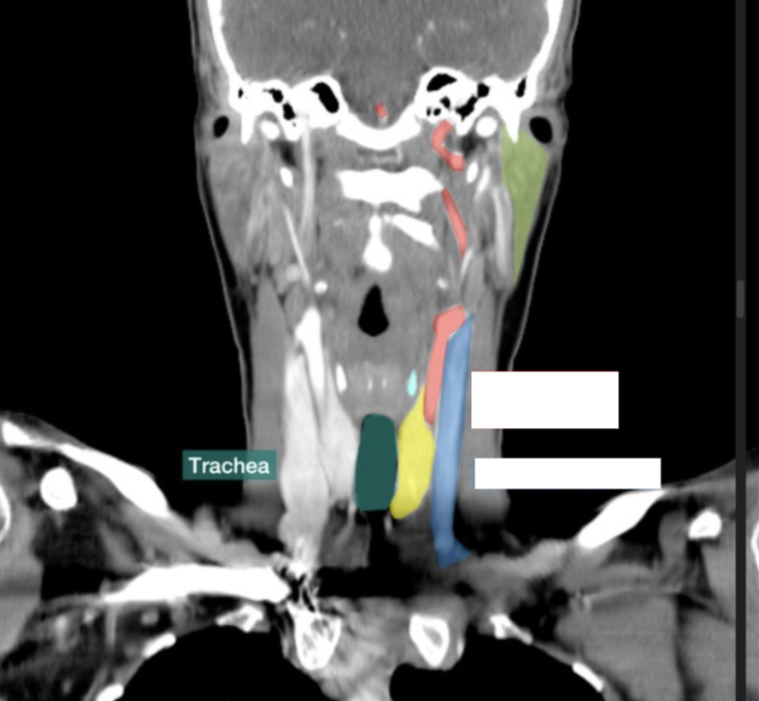

Please label